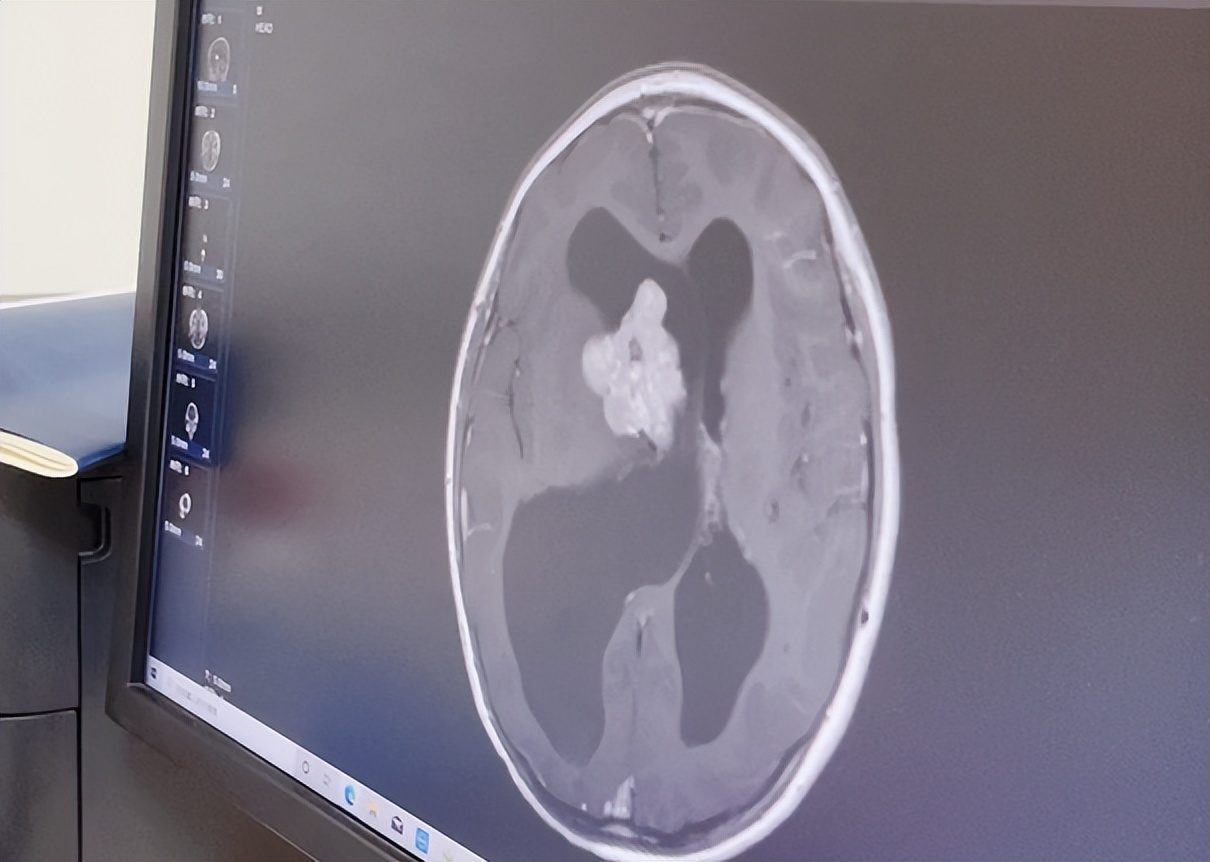

▲术前检查提示:右侧脑室巨大占位,形态不规则,分叶状,强化显著,肿瘤显著压迫周围重要脑组织,内有结节状钙化,梗阻性脑积水,双室间孔堵塞,颅骨薄。

当看到小刘的脑部核磁影像结果后,河南三博脑科医院神经外科主任刘宁不禁捏了把冷汗,长期的脑积水使小刘颅内压增高,头骨变得像“蛋壳”一样轻薄脆弱,稍有不慎,轻则频繁头痛、呕吐,磕碰引起颅骨骨折及脑组织损伤,重则脑积水突然加重,出现昏迷、呼吸心跳骤停,危及生命安全。

刘宁主任说:“手术难点和要点在于,一方面脑室明显扩大,肿瘤把双室间孔堵塞,梗阻性积水,两边的脑室显著扩张,脑压很高,同时脑骨长期受压,颅骨薄的像鸡蛋壳一样轻薄脆弱,术中稍有不慎极易造成骨折或颅脑损伤,可以说是非常危险的。”

“另一方面,肿瘤体积大,位置深在,周围解剖结构重要且复杂;肿瘤血运非常丰富,与深部引流静脉粘连显著且局部包裹,深部引流静脉的损伤,会造成致命性的脑水肿。”

另外,肿瘤严重压迫尾状核、内囊、丘脑的结构并与之粘连异常紧密,术中稍有不慎极易造成这些结构的损伤,导致术后灾难性的并发症,比如偏瘫、语言障碍、认知功能障碍、昏迷甚至死亡。